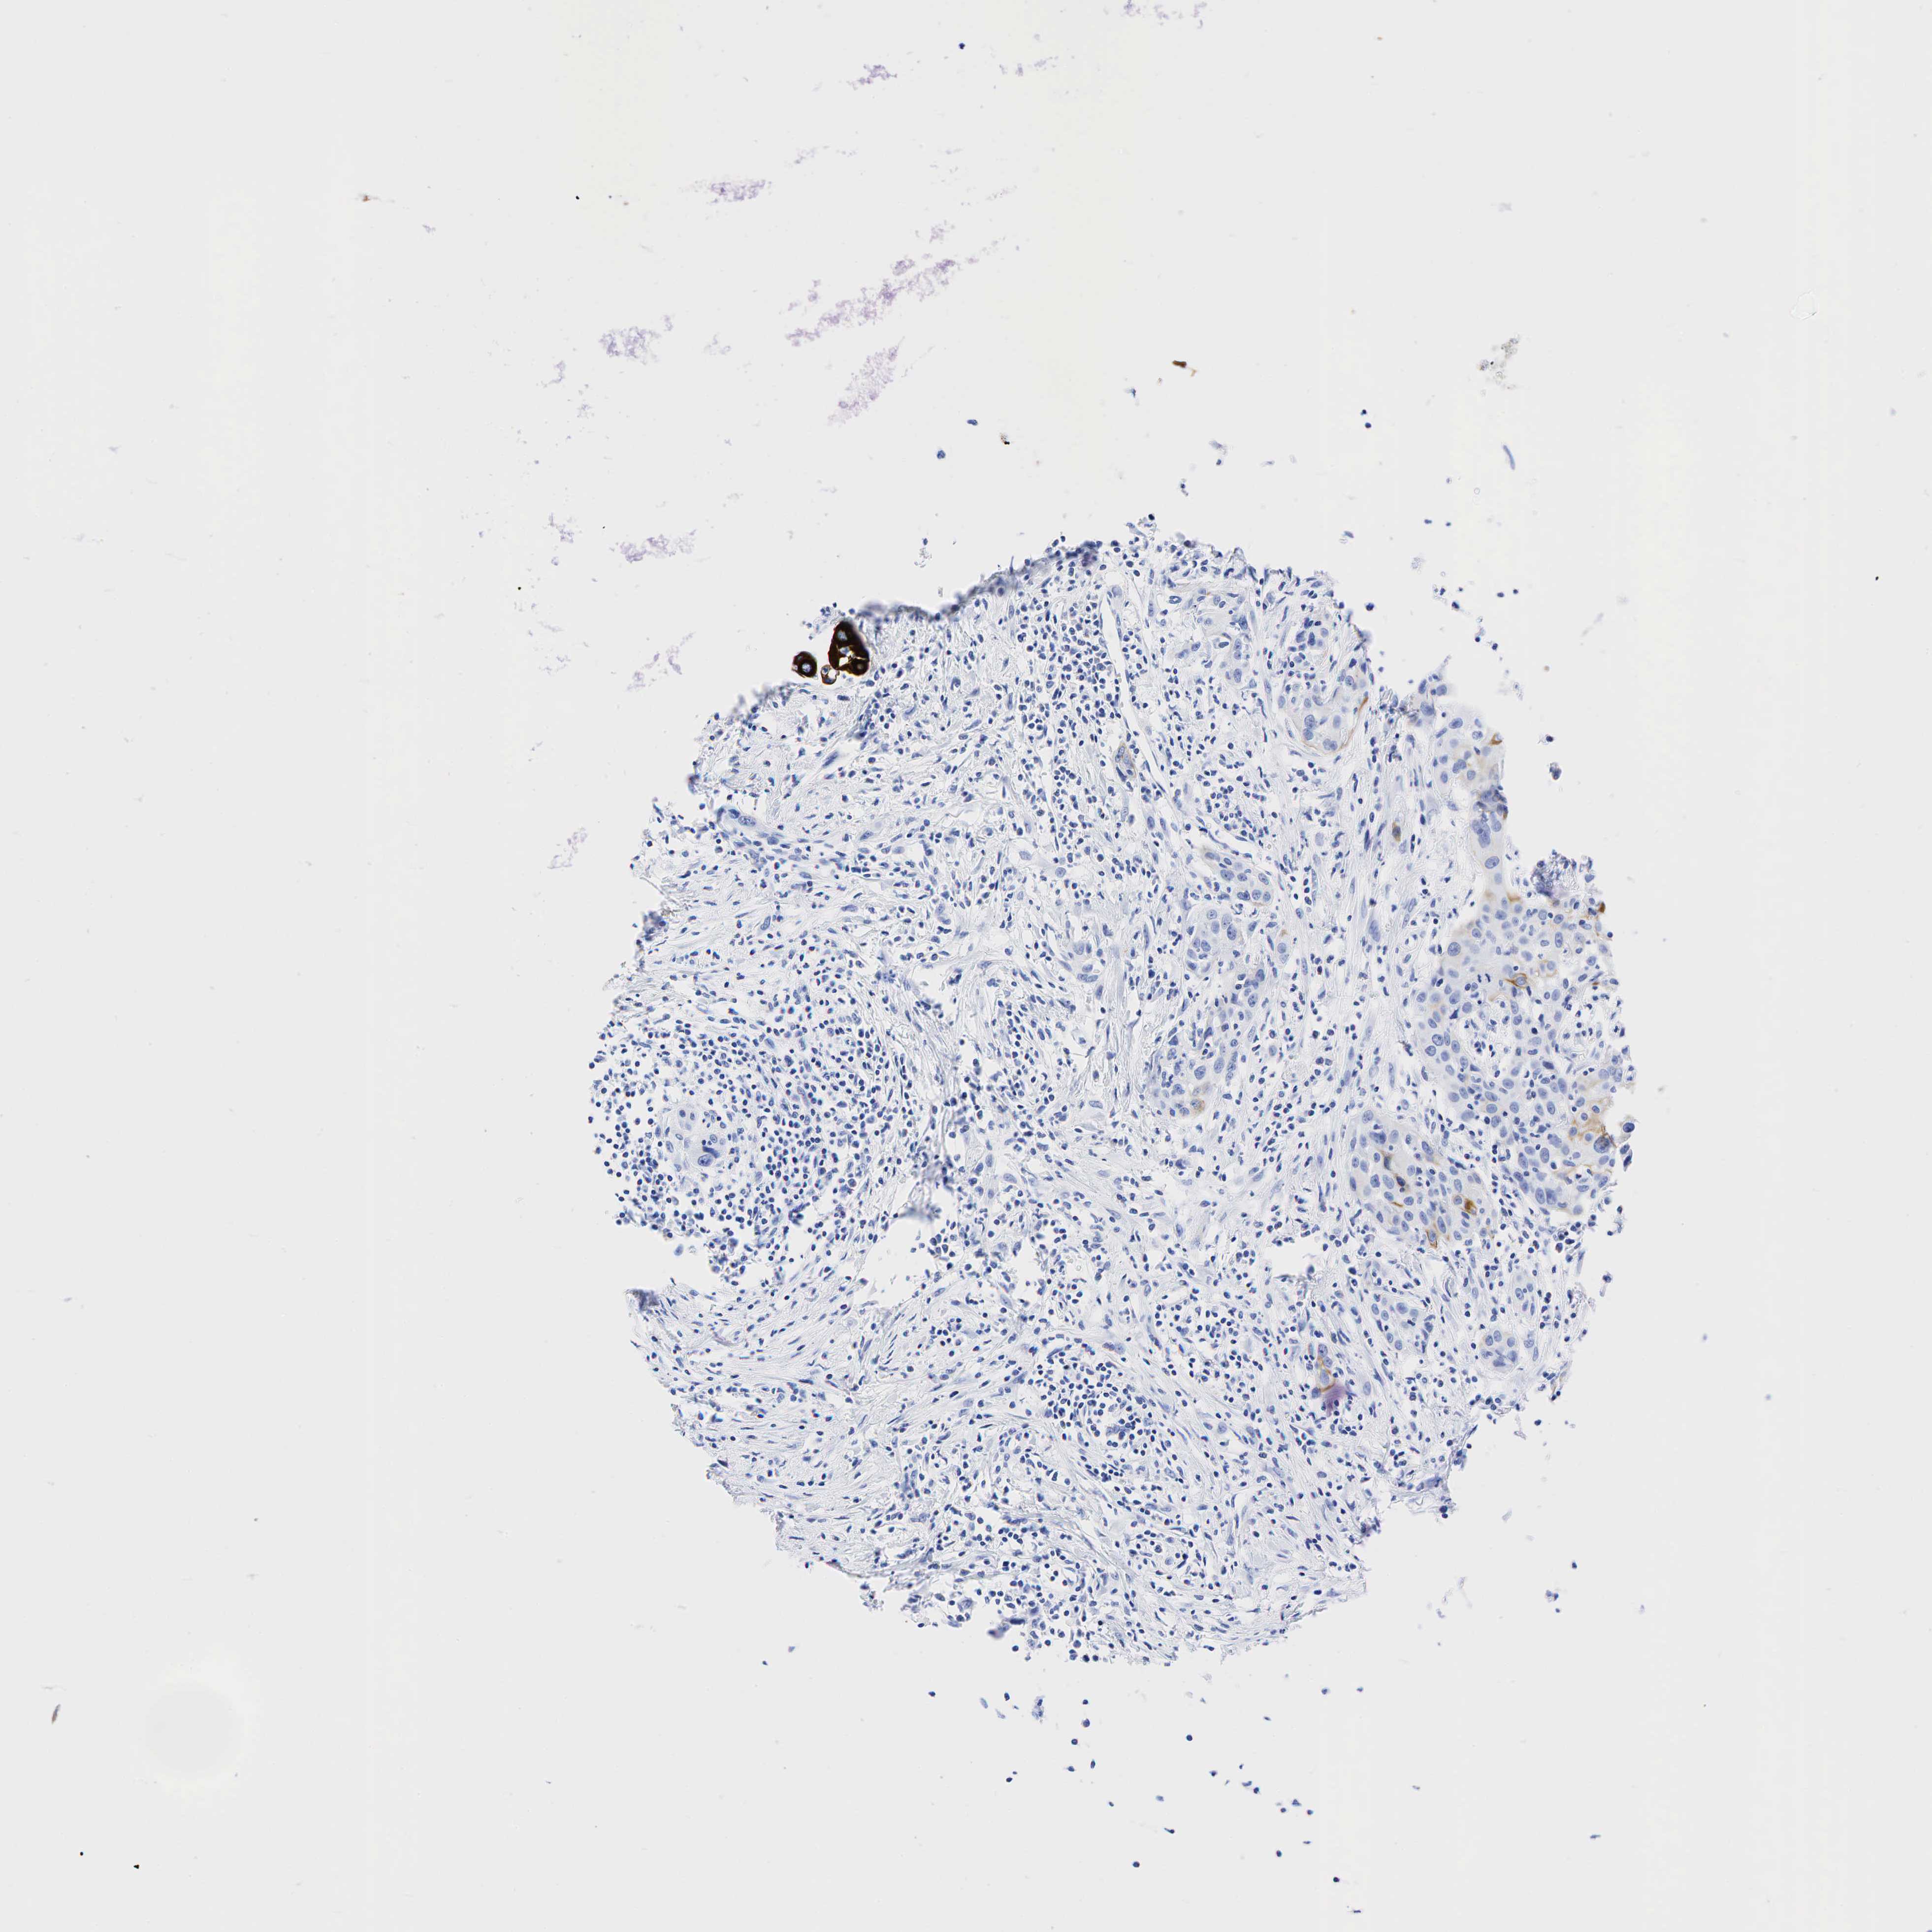

UROTHELIAL CANCER - Protein expressioni

A mouse-over function shows sample information and annotation data. Click on an image to view it in a full screen mode. Samples can be filtered based on level of antibody staining by selecting one or several of the following categories: high, medium, low and not detected. The assay and annotation is described here.

Antibody stainingi

Antibody staining in the annotated cell types in the current human tissue is reported as not detected, low, medium, or high, based on conventional immunohistochemistry profiling in selected tissues. This score is based on the combination of the staining intensity and fraction of stained cells.

Each image is clickable and will lead to virtual microscopy that enables deeper exploration of all samples and also displays staining intensity scores, fraction scores and subcellular localization as well as patient and tissue information for each sample.

Antibody HPA002465

Antibody CAB000031

Staining

High

Medium

Low

Not detected

Intensity

Strong

Moderate

Weak

Negative

Quantity

>75%

75%-25%

<25%

None

Location

Nuclear

Cytoplasmic/membranous

Cytoplasmic/membranous,nuclear

Urothelial carcinoma, High grade

Urothelial carcinoma, Low grade

Adenocarcinoma, NOS